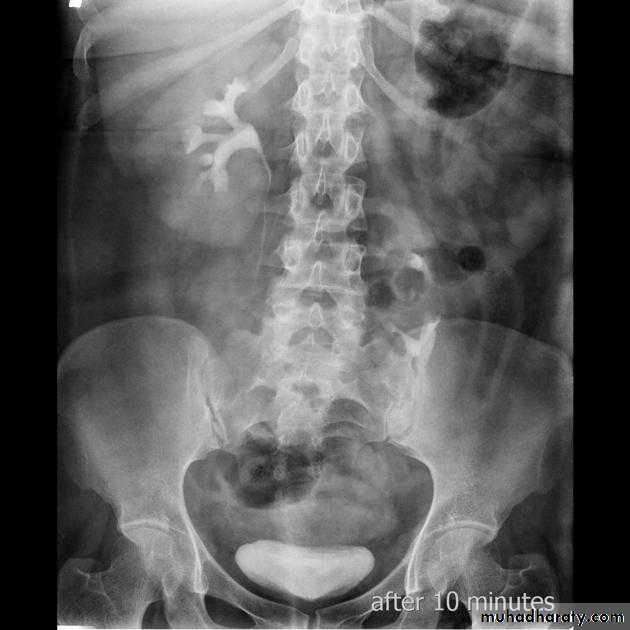

Infantile hydronephrosis ( PUJ OBSTRUCTION ):

IVU shows :

Marked dilatation of pelvis and may be extra-renal.

Calyceal dilatation is late and in advanced cases form foot shape PCS

The ureter is not seen and when it is seen looksnormal .

Delayed film with I.V. diuretic produce gross dilatation .